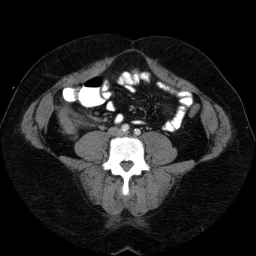

This is an image from a contrast enhanced abdominal CT.

These are images from a contrast enhanced abdominal CT.

Fluid in the right paracolic gutter, and a thickened, inflamed appendix with thickening of the adjacent cecal wall.

Differential: Acute appendicitis is by far the most likely diagnosis.

No appendicolith is seen in this case.

The appendix is normally less than 7 mm in diameter, or if fluid filled, the wall can be up to 3mm thick. This appendix is distended, and the adjacent stranding and fluid indicates the inflammatory process which is causing peritoneal irritation and pain. Here is a series of images showing a normal appendix using similar technique. Note the thin walls of the normal appendix.